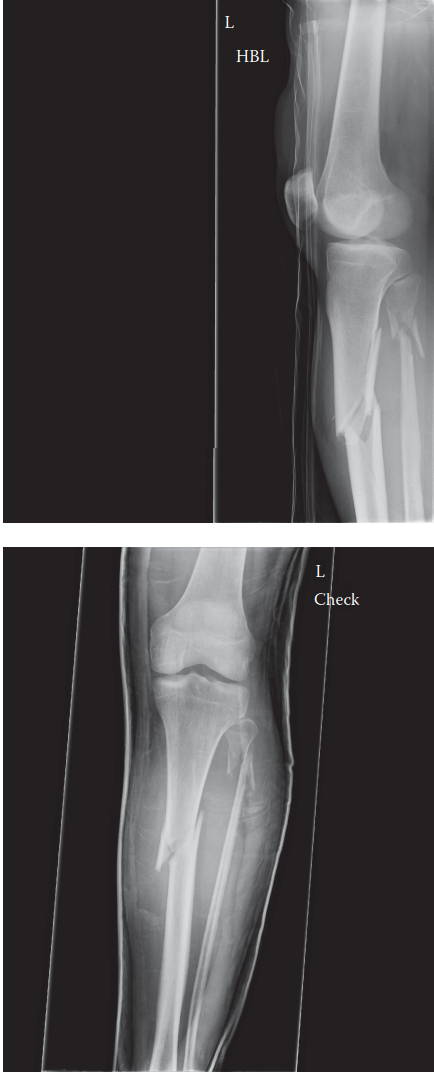

Explore a detailed academic case study of a 38-year-old male with a high-energy proximal tibial diaphyseal fr…

Case study of a high-energy comminuted tibial diaphyseal fracture with angulation and rotational deformity. C…